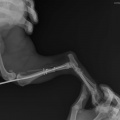

Koer on opereeritud.

Tagumise käpa luumurd.

Koerake sattus varjupaika vigastatud käpaga. Ülevaatusel selgus, et koera käpal on mitmekordne luumurd. Pidime paigaldama ka kateetri, kuna ta ei saanud pissida (ilmselt autolöögist põhjustatud kusepõie atoonia).

Собака поступила в приют с множественным переломом ноги. Не могла пописать (видимо был удар машины и, как результат, атония мочевого пузыря). Нога в очень тяжёлом состоянии, и завтра мы кладём собаку на операционный стол.